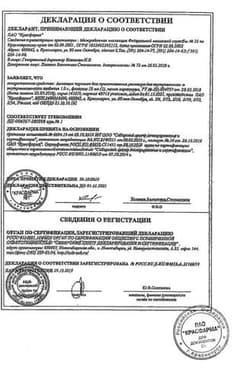

Сертификаты